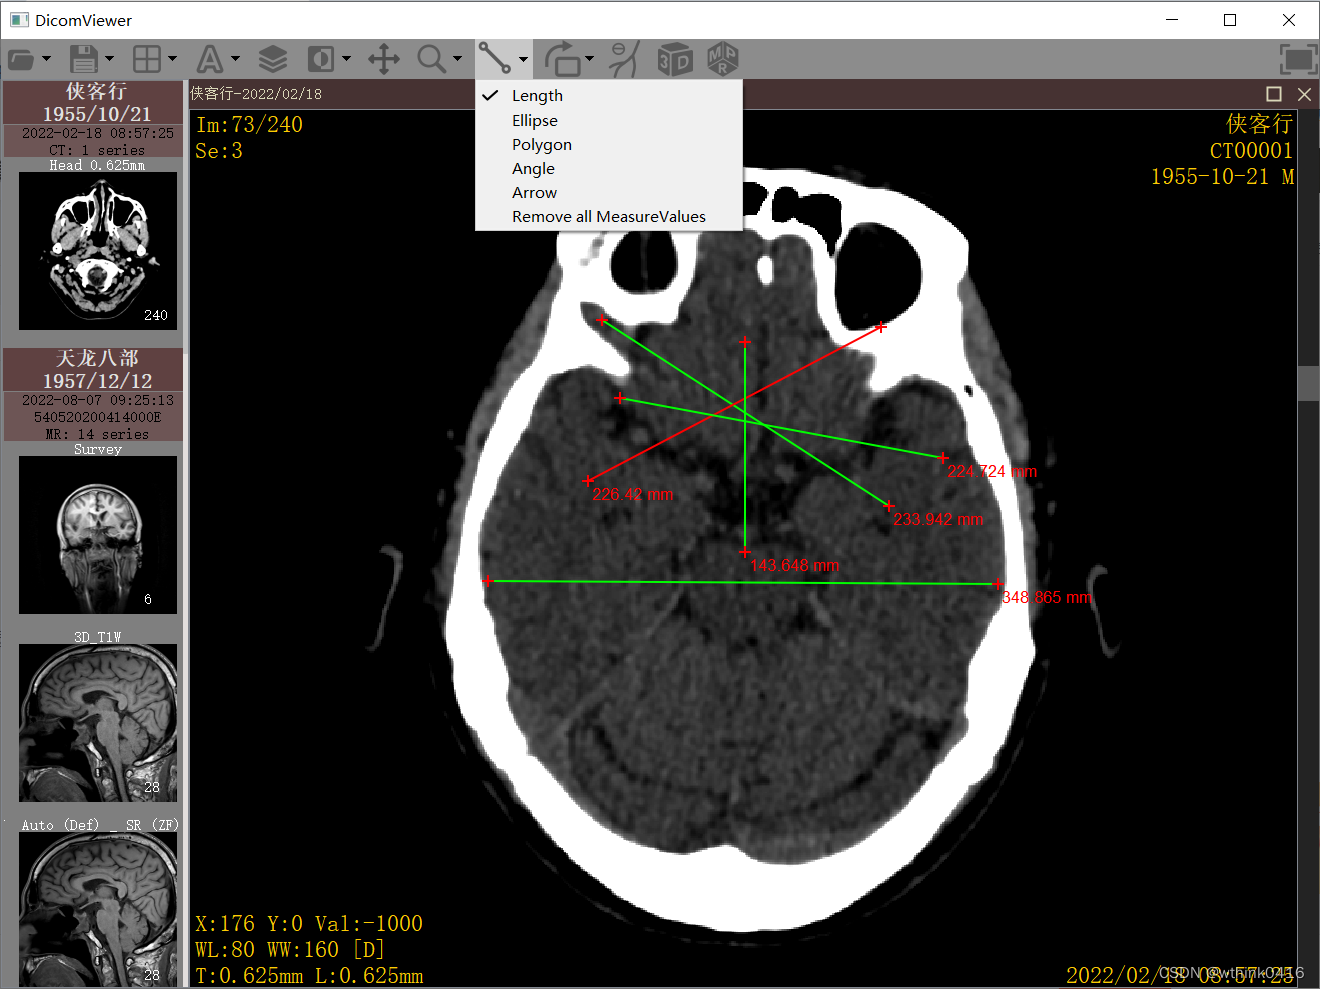

8、点击![]() 线段图标,可实现两点间的长度测量,测量值选中后可以调整、平移、删除等,时间匆忙了一些,暂时只实现了长度的测量值,后续慢慢会把其他测量值补充上

线段图标,可实现两点间的长度测量,测量值选中后可以调整、平移、删除等,时间匆忙了一些,暂时只实现了长度的测量值,后续慢慢会把其他测量值补充上